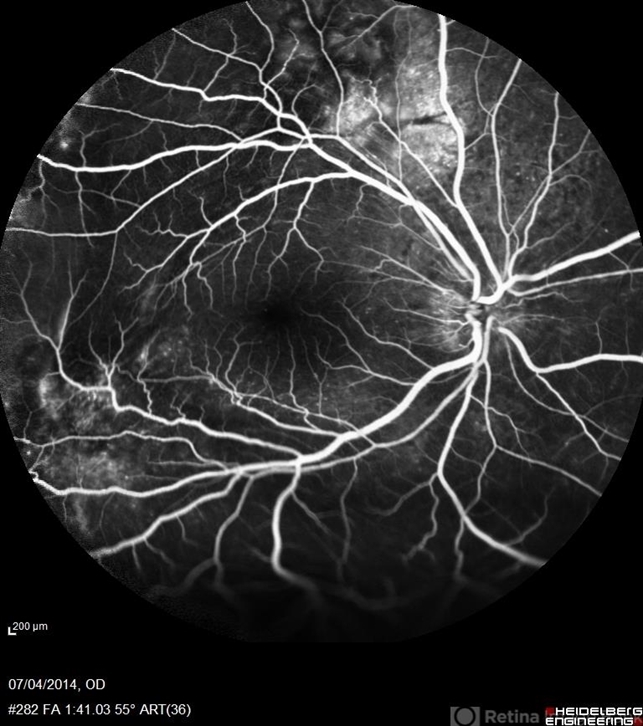

- VogtKoyanagiHarada

- multifocal central serous chorioretinopathy (CSCR)

- Avris Romario Diparaja Siahaan, Klinik Mata Nusantara

Scanning laser ophthalmoscope

Heidelberg HRA + OCT Spectralis - Description

- FA a 38-year-old man with multifocal CSR and inferior exudative retinal detachment on both eyes (Harada Syndrome).